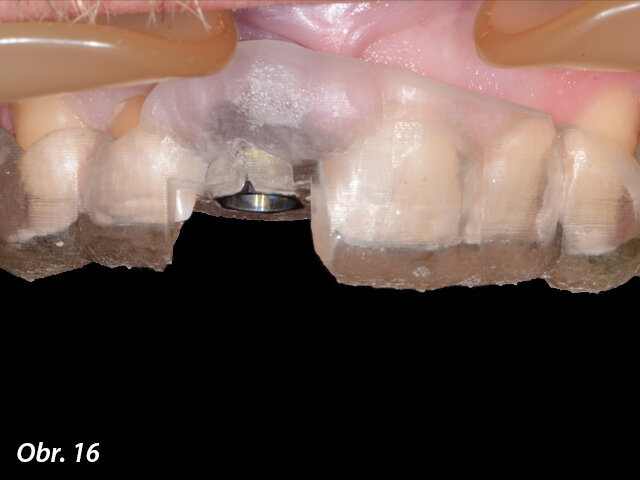

Plánování tvaru a velikosti budoucí CSD/CAM e.max korunky v programu In Lab 16 na základě obdrženého souboru Core File.

Po naplánování pozice implantátu a budoucí korunky byla všechna data odeslána do Belgie s cílem vyrobit chirurgickou šablonu. Když byla chirurgická šablona navržena, byly soubory odeslány do frézovacího centra ATLANTIS ve Švýcarsku s cílem vytvořit individuální abutment. Po schválení virtuálního projektu abutmentu byl během hodiny vytvořen a bezprostředně odeslán na kliniku soubor, tzv. Core File. Díky tomu zubní technik mohl naplánovat a vyfrézovat dočasnou korunku v systému CAD/CAM Sirona CEREC. Tato šroubovaná korunka bez okluzních kontaktů byla zhotovena z bločku keramiky e.max a na individuální abutment Atlantis Custom Base (s povrchem TiN) byla nacementována mimo dutinu ústní. Všechny komponenty – chirurgická šablona SIMPLANT, abutment Atlantis Custom Base i dočasná korunka, byly zhotoveny před chirurgickým výkonem.